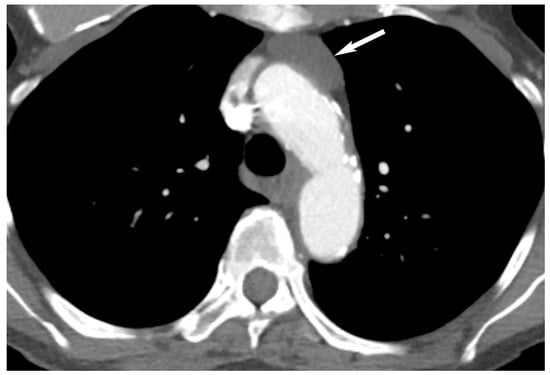

Visceral (Middle) Compartment

8. Cystic Lesions

9. Hypervascular Lesions

10. Esophageal Lesions